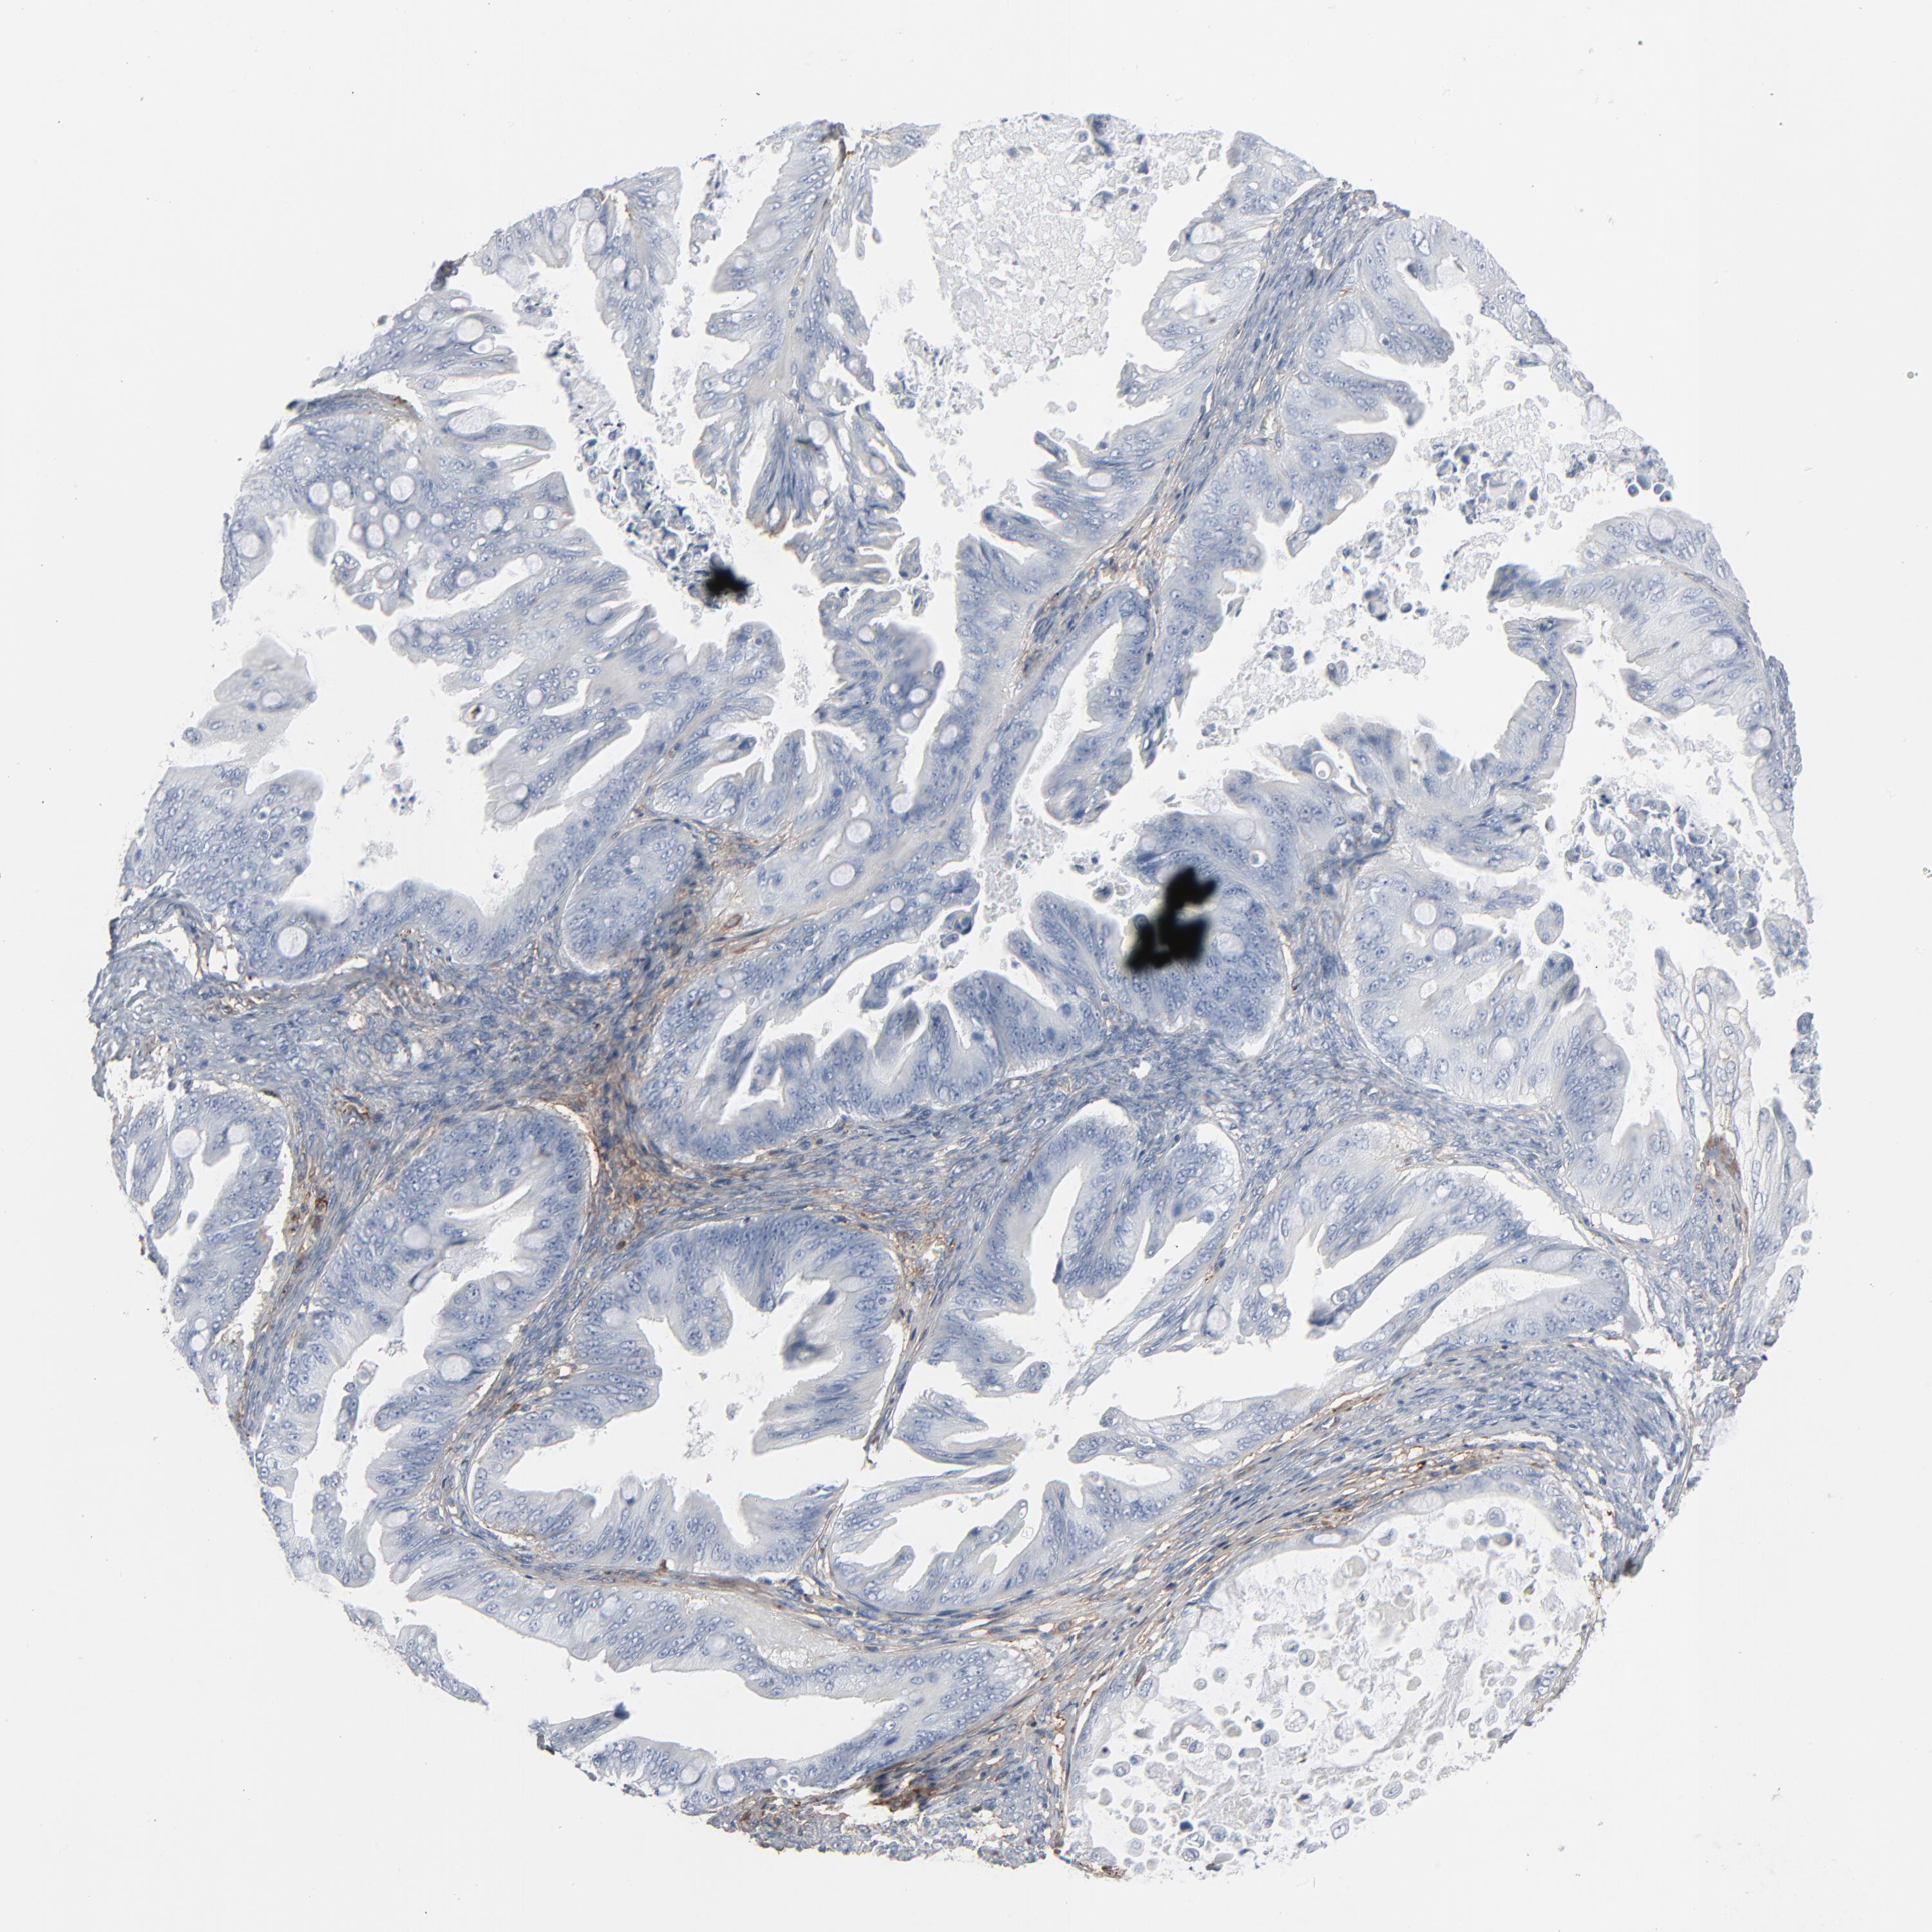

OVARIAN CANCER - Protein expressioni

A mouse-over function shows sample information and annotation data. Click on an image to view it in a full screen mode. Samples can be filtered based on level of antibody staining by selecting one or several of the following categories: high, medium, low and not detected. The assay and annotation is described here.

Note that samples used for immunohistochemistry by the Human Protein Atlas do not correspond to samples in the TCGA dataset.

Antibody stainingi

Antibody staining in the annotated cell types in the current human tissue is reported as not detected, low, medium, or high, based on conventional immunohistochemistry profiling in selected tissues. This score is based on the combination of the staining intensity and fraction of stained cells.

Each image is clickable and will lead to virtual microscopy that enables deeper exploration of all samples and also displays staining intensity scores, fraction scores and subcellular localization as well as patient and tissue information for each sample.

Antibody HPA003157

Antibody CAB003678

Carcinoma, endometroid

Cystadenocarcinoma, serous, NOS

Cystadenocarcinoma, mucinous, NOS